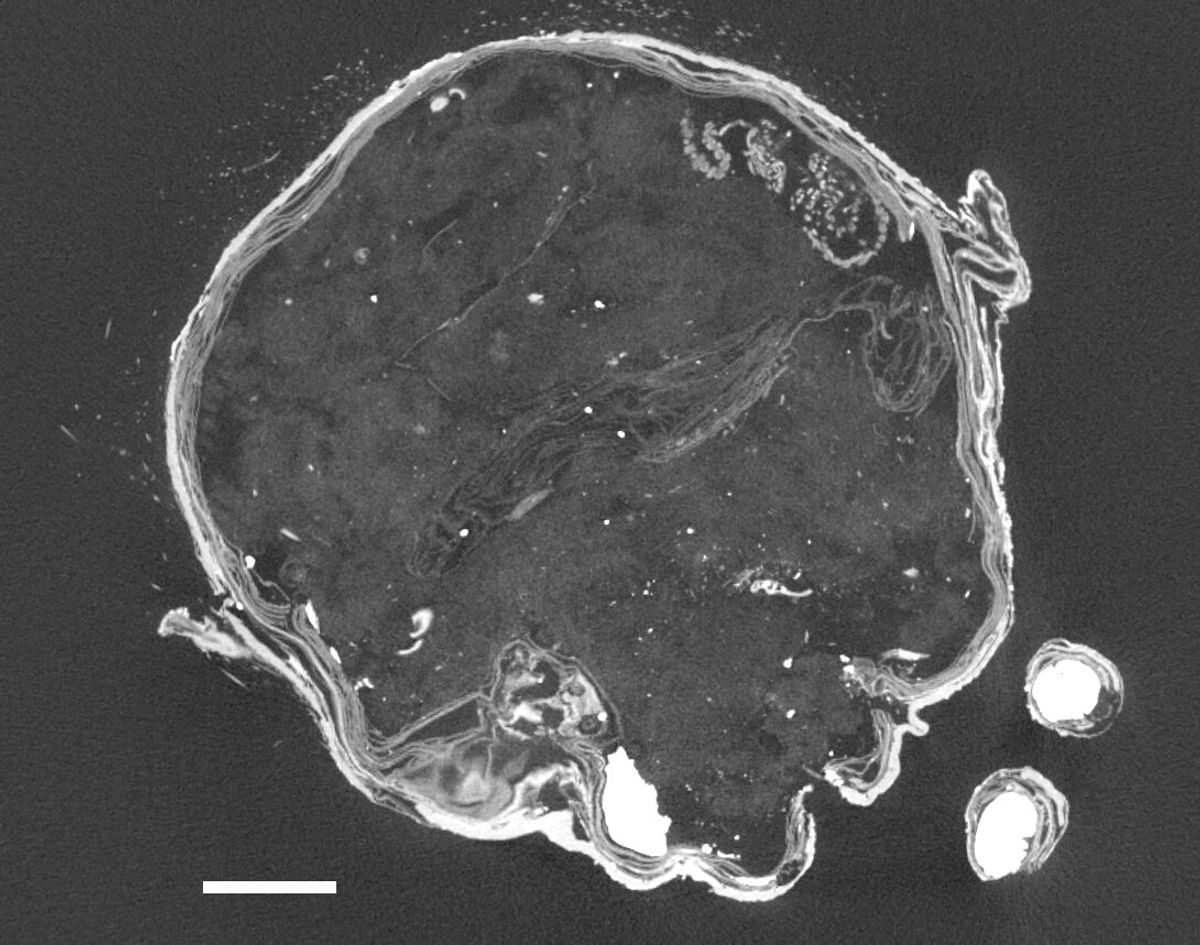

Дослідники з Університету науки і мистецтв Курасікі в Японії розкрили таємницю маленької мумії русалки, відомої, що зберігалася в храмі Ендзуін в Асакуті. Результати дослідження показали, що, на відміну від інших подібних зразків, верхня частина опудала була зроблена не з висушеної мавпячої плоті, а з паперу, тканини та бавовни.

Нижня частина опудала була зроблена з риб’ячого хвоста. Радіовуглецевий аналіз показав, що мумія була створена наприкінці 19 століття.

Знахідка дослідників з Університету Курасікі відрізняється тим, що для верхньої частини опудала використали папір, тканину й бавовну, що є доволі незвичним. Водночас саме опудало виглядає доволі реалістично, як і задумували творці фейку.